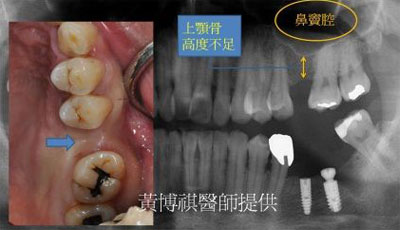

一般而言,口腔內的上顎後牙區,和鼻竇腔只有一層薄薄的上顎骨相隔。因此,上顎後牙區在做 植牙手術之前,都需要先進行鼻竇增高術,來增加上顎骨厚度。 |

微創型鼻竇增高術是利用"鼻竇挺"輕輕將人工骨粉推入鼻竇腔。由連續X光片可以看到,人工骨 粉慢慢地被送進鼻竇腔中。 |

待完成鼻竇增高術後,便可植入適當長度的人工牙根。 |